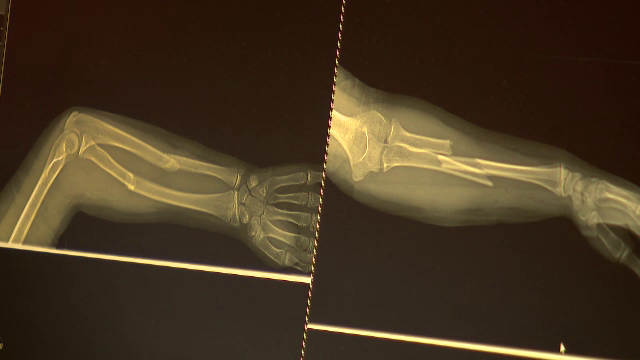

Fracturile grave cu care s-au ales zeci de copii în urma „Superman Challenge”, de pe TikTok. „Se vindecă într-un an de zile”

Crește numărul copiilor răniți în urma jocului ”Superman challenge”, o provocare de pe TikTok. ...

Mai mulți copii au ajuns la spital cu fracturi grave după ce au făcut Superman Challenge de pe TikTok

Trei copii, cu vârste cuprinse între 11 şi 14 ani, au ajuns la Spitalul Judeţean Arad, din cauza provocării ...

Medicii trag un semnal de alarmă după ce zeci de copii s-au ales cu fracturi după „Superman challenge”

''Superman challenge'', o nouă provocare lansată pe TikTok, a trimis la spitalul Grigore Alexandrescu din Capitală zeci ...

„Superman Challange”, provocarea de pe TikTok care a băgat în spital 20 de copii într-o singură zi în București

Superman Challenge este o provocare în trend pe TikTok, dar s-a dovedit a fi periculoasă pentru copiii care o ...

Peste 20 de copii au ajuns la spital într-o singură zi, după provocarea „Superman”, de pe TikTok. Au suferit răni grave

Peste 20 de copii au ajuns într-o singură zi cu răni grave la Spitalul Grigore Alexandrescu din Capitală, după o ...